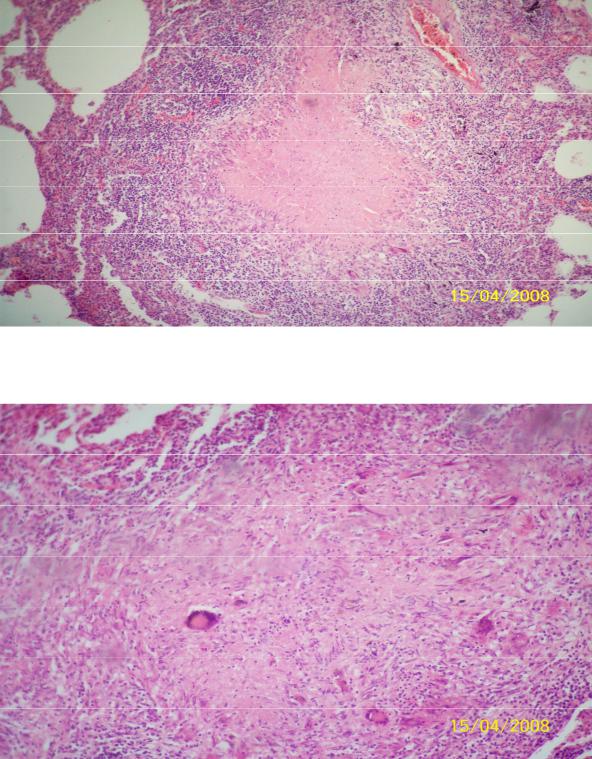

Микроскопический взгляд на мишитарный туберкулез легкого: фотодокументация

Раздел: Снимки-откровения